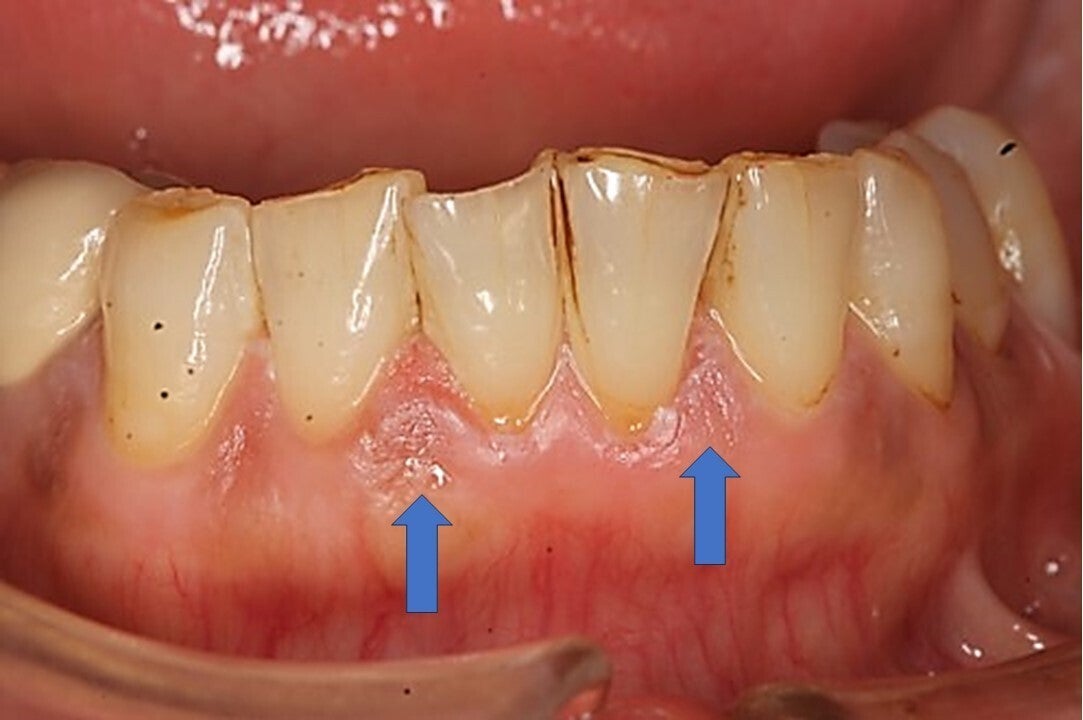

歯ブラシが原因と思われる傷

自分では見えない部分 やり過ぎになってしまう

開業以来、日々の診療の中で、磨き過ぎが原因と考えられる方が多数、来院されます。虫歯も無い、歯周病も無い、しかし、違和感や症状を訴える方がたくさんいらっしゃいます。

よく観察すると、歯ぐきに小さな傷があり、磨き過ぎが原因ではないかと考えました。それから辛抱強く歯みがき指導を行っていくと、大きな処置をしなくても、症状が軽減される方が増えていきました。

右利きの人は左側が磨きやすいので強くなる傾向がある

着色を取ろうとして毎日磨いたため